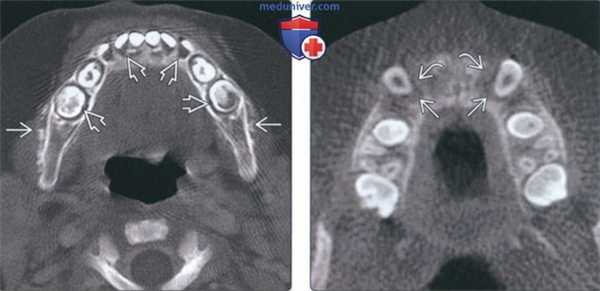

(Слева) На аксиальной КТ нижней челюсти в костном окне у ребенка младшего возраста определяется отсутствие твердой пластинки и расширение пространств периодонтальной связки. Также визуализируется диффузный участок снижения плотности с периостальной реакцией в виде «вставших дыбом волос».

(Справа) На аксиальной КЛКТ у мальчика 11 лет, которому планировалось ортодонтическое лечение, определяется утрата костной ткани в альвеолярном отростке вследствие лейкоза. Изменения имитируют поражение периодонта, которое обычно не наблюдается у детей. Твердая пластинка не визуализируется, пространава периодонтальной связки расширены.